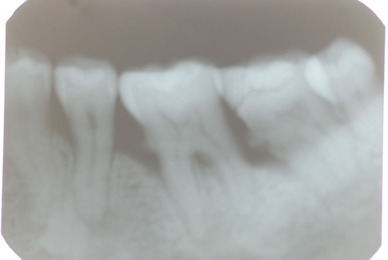

![3497_965331090210210_1701298804172117471_n[1]](https://livedoor.blogimg.jp/netdental/imgs/c/d/cd16b73e-s.jpg)